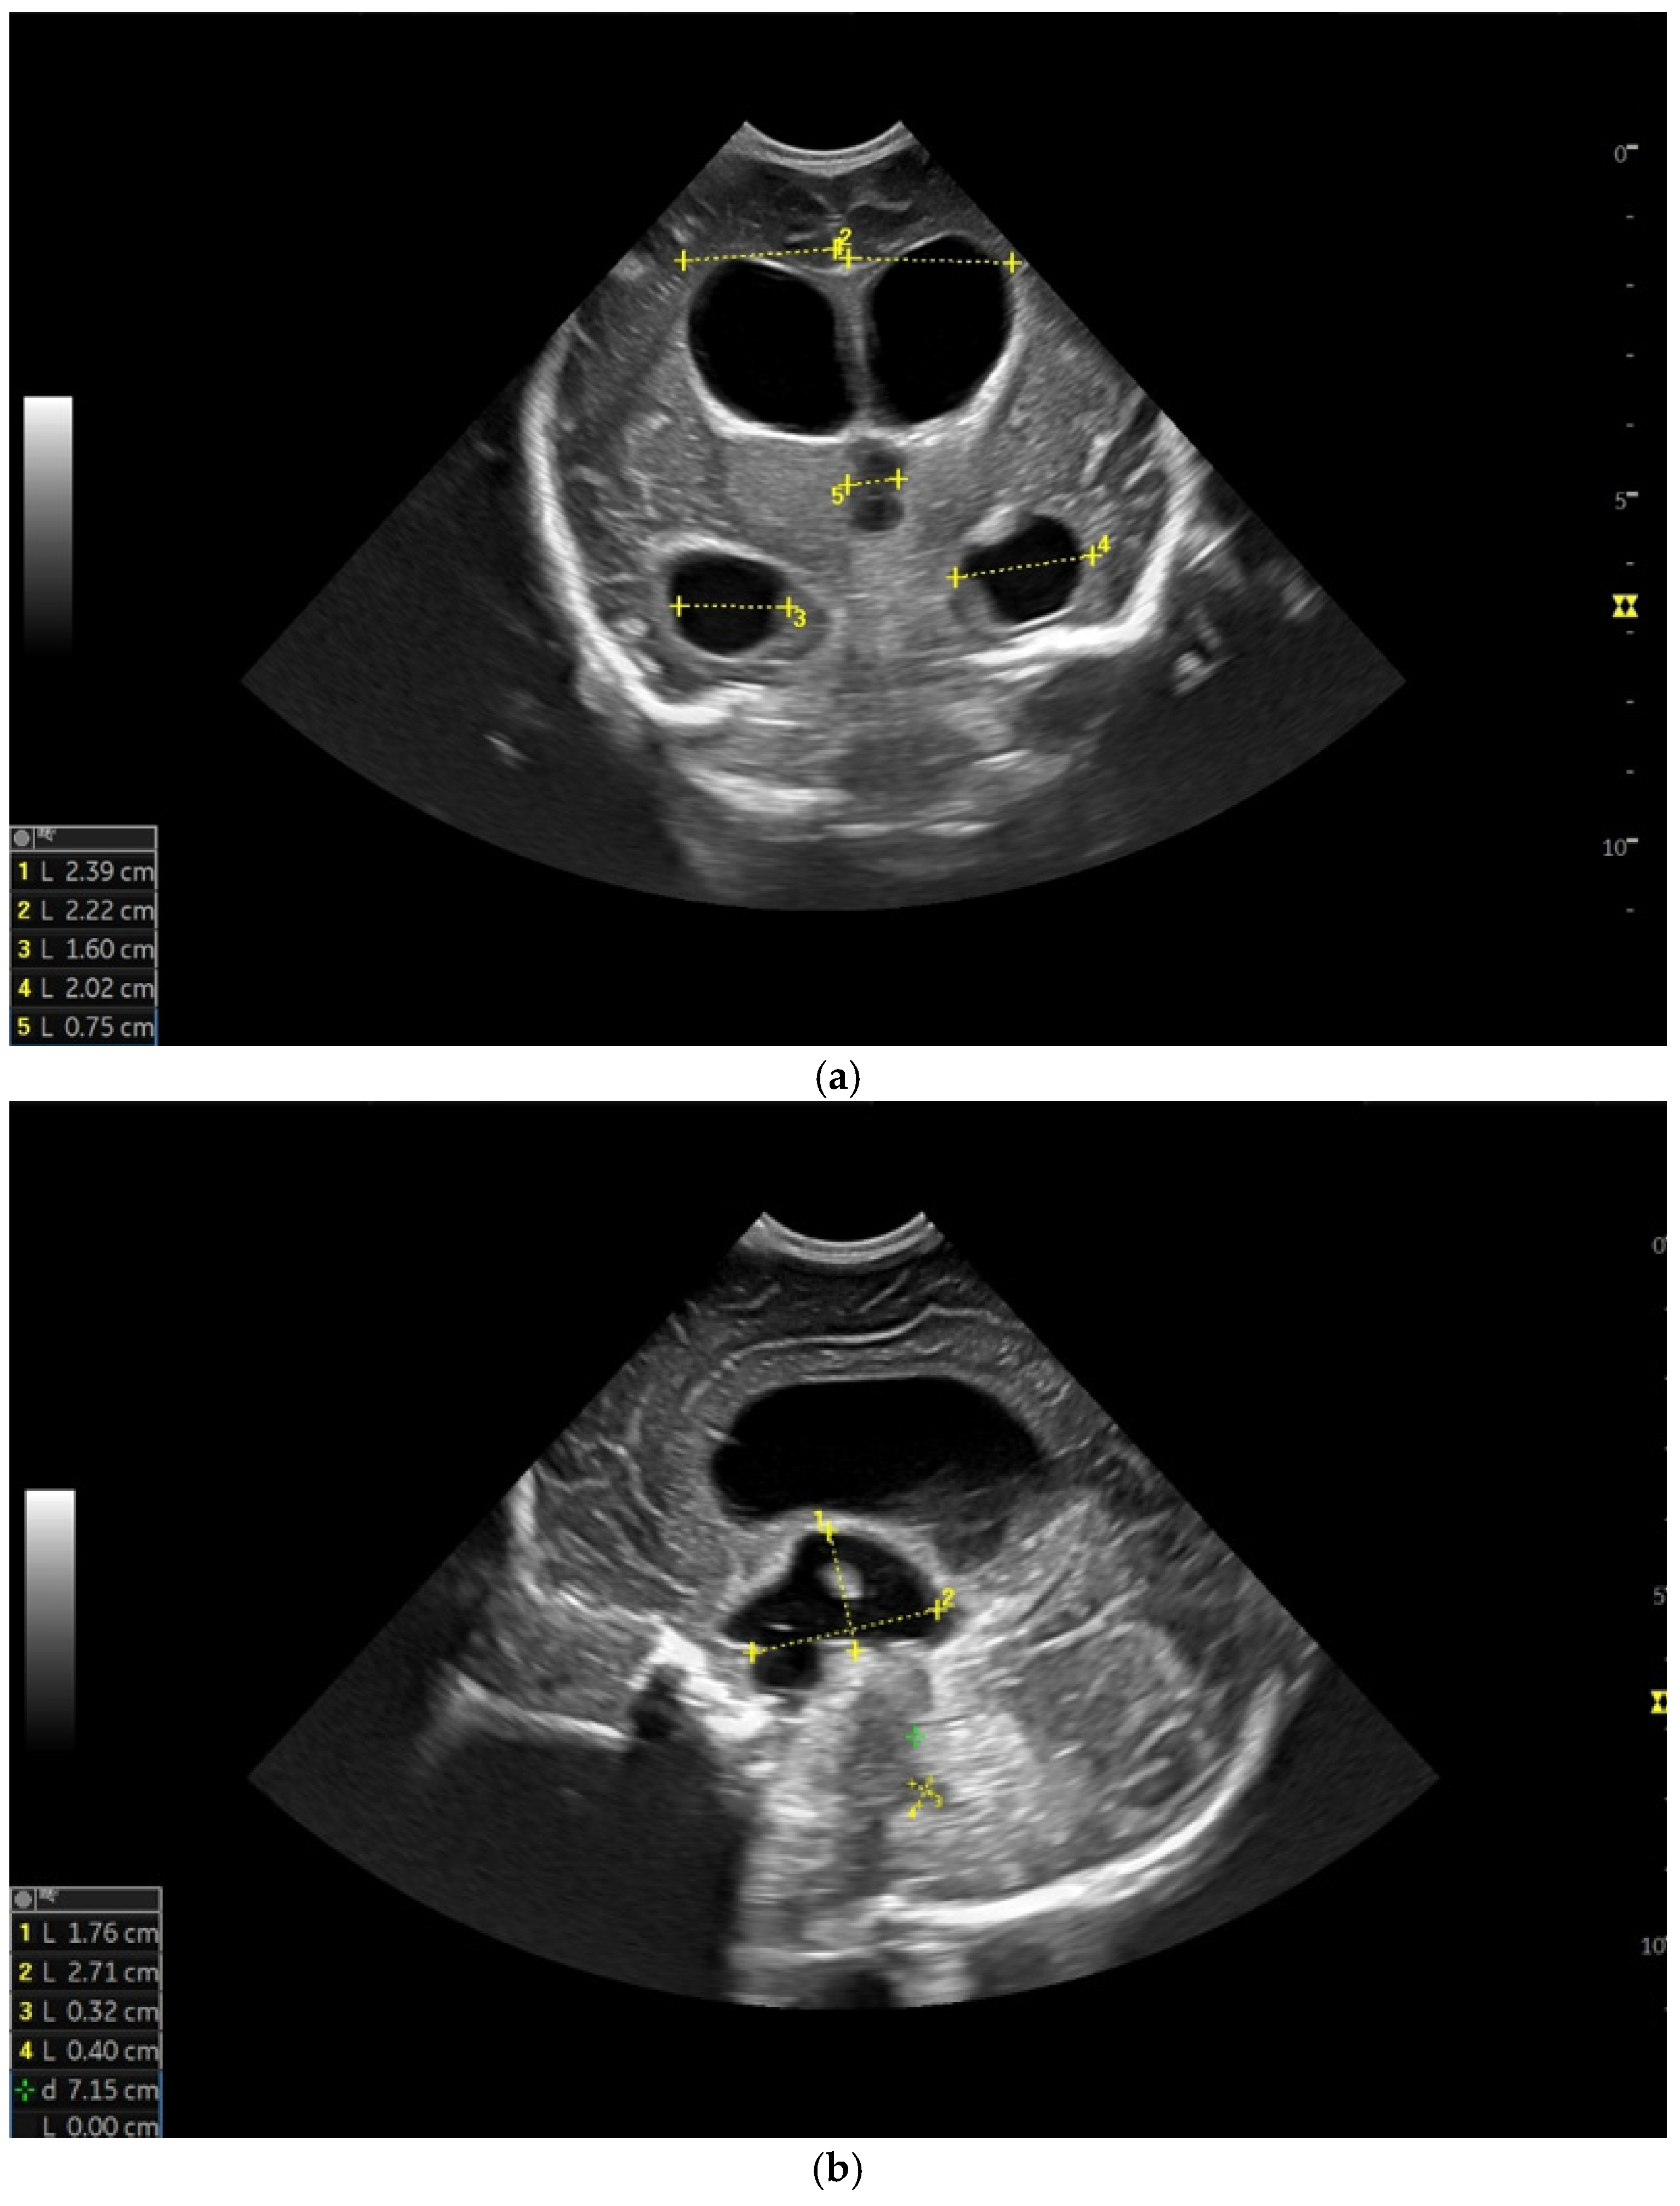

Figure 4.

(a) Cranial ultrasound. Coronal view. Lateral ventricles and third ventricle enlargement. L1, L2—Levine index measurement. L3, L4—posterior horn of the lateral ventricles’ width measurement. L5—third ventricle width measurement (personal image collection). (b) Cranial ultrasound. Sagittal view. Enlarged third and fourth ventricles. L1, L2—third ventricle measurements. L3, L4—fourth ventricle measurements (personal image collection). (c) Cranial ultrasound. Sagittal view. Enlarged lateral ventricles. Up—left ventricle. Down—right ventricle (personal image collection). (d) Cranial ultrasound. Coronal view. Punctuate hyperechoic images were observed in the right lobe (personal image collection). (e). Up left—MRI T1 sequence. Up right—MRI T2 sequence—susceptibility weight imaging (SWI). Down—CT scan. Transversal view. Yellow arrows—multiple calcifications can be seen in the CT scan (personal image collection). (f) Cranial ultrasound. Coronal view. Lateral ventricles. L1, L2—Levine index measurement. L3, L4—anterior horn width measurement. Blue arrow—intraventricular shunt (personal image collection). (g) Cranial ultrasound. Sagittal view. Thalamo-occipital distance measurements. Up—right ventricle. Down—left ventricle (personal image collection).

Five weeks after birth, the patient presented for the first cranial ultrasound examination, which revealed enlarged ventricles and the presence of a hyperechoic image in the right frontal lobe, suggestive of calcifications. The parenchymal tissue was reduced (Figure 4a–d). The anterior fontanelle was wide, with large sutures. The neurological assessment showed that the infant could keep eye contact and would also hold its head during the traction-to-sit maneuver but was not able to lift its head while in the prone position. The passive tone assessment showed the “scarf sign”, with the elbow at the midline and a popliteal angle range for both legs of 90–100°. Deep tendon reflexes were present. The general movement (GM) assessment revealed a poor repertoire pattern with minimal mobility in the lower limbs. Treatment for Toxoplasma was initiated.

At six weeks after birth, an MRI scan was performed, while a CT scan was performed at 14 weeks of life, both providing valuable information regarding the sequelae of Toxoplasmosis (Figure 4e). Even though a few signs were observed on the MRI, the CT scan better outlined the presence of the parenchymal calcifications. A neurosurgical intervention was intended, a ventricle puncture was performed, and a shunt was placed in the right ventricle. The cranial ultrasound at two months of life did not show notable improvements, however (Figure 4f,g). The neurological examinations showed axial hypotonia and limb hypertonia.